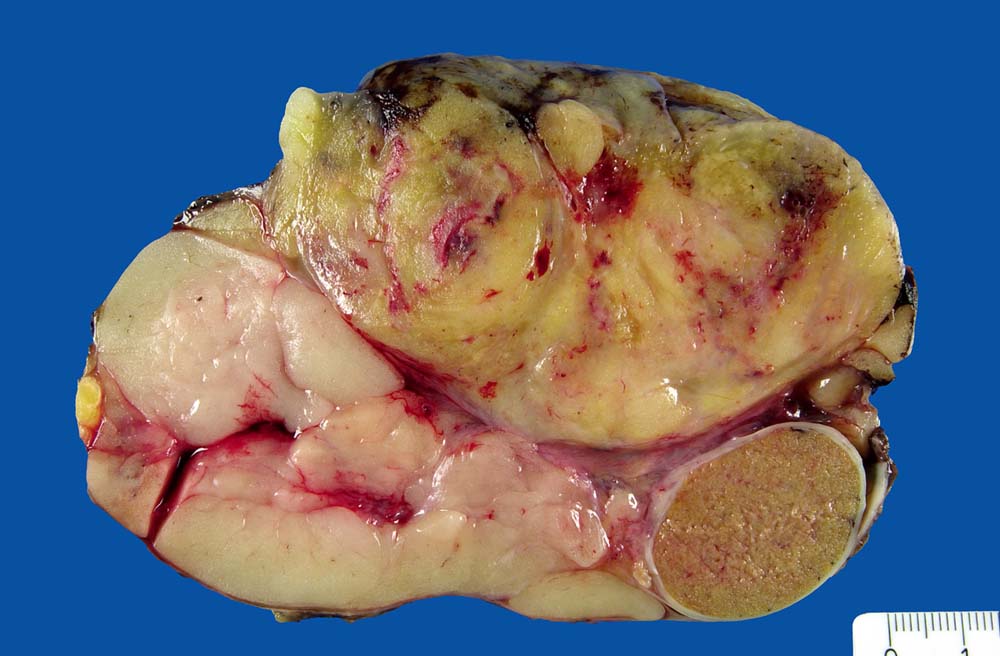

Hoch differenziertes Liposarkom

Der tumorfreie Hoden wird umgeben von teils fettähnlichem, teils fleischig weisslichem Tumorgewebe.

Gut differenziertes Liposarkom der peritestikulären Weichteile ohne Nekrosen. FNCLCC=1+0+1=2, maximaler Tumordurchmesser 11cm.

Hodentumor rechts.